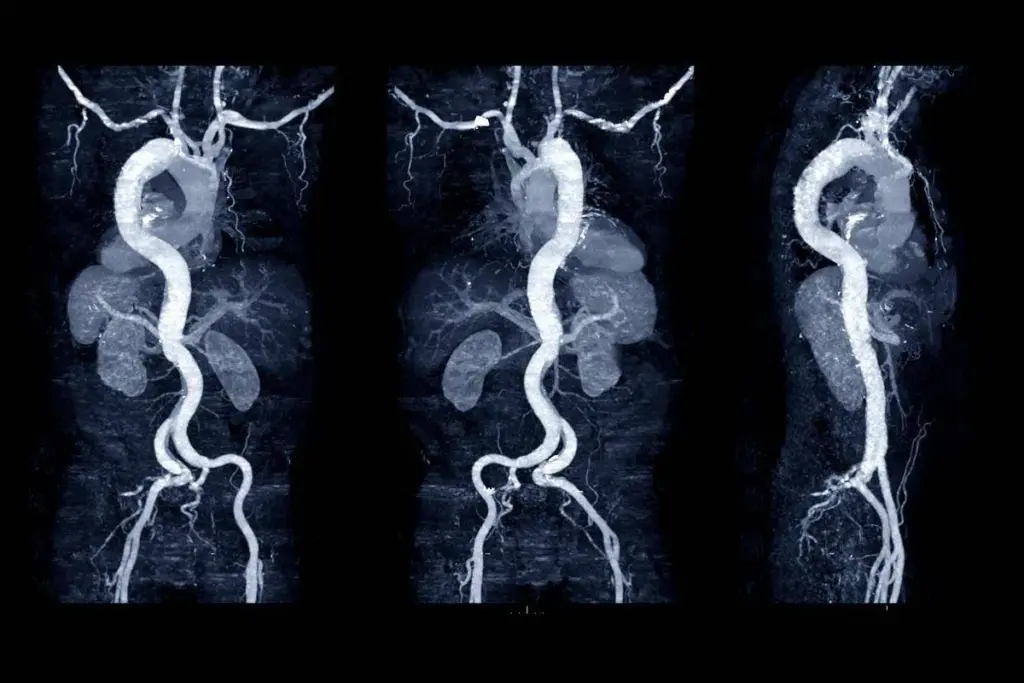

It’s important to know about the dangers of aortic aneurysms to catch them early. An aortic aneurysm is a bulge in the aorta. This is the main blood vessel that carries blood from the heart to the rest of the body.

An aortic aneurysm can happen anywhere along the aorta. This blood vessel runs from the heart through the chest and abdomen. If it happens in the chest, it’s called a thoracic aortic aneurysm. If it’s in the abdomen, it’s an abdominal aortic aneurysm.

Imaging tests like CT scans, MRI, or ultrasound are used to diagnose. Clinical evaluation and patient history are also important.